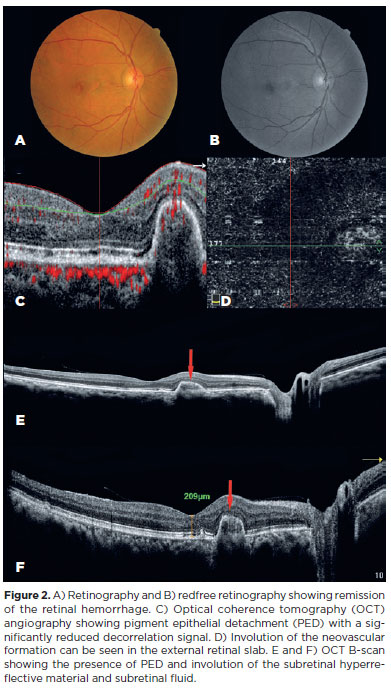

The pitchfork sign (PS) is a distinctive finding on optical coherence tomography (OCT) that is characteristic of type 2 macular neovascularization (MNV) secondary to punctate inner choroidopathy (PIC)(1-3). A 57-year-old male presented to us with complaints of blurring of vision in the right eye (OD) for one month. At the time of admission, the best-corrected visual acuity was 20/150. OCT and OCT angiography revealed a PS (Figure 1). Thus, the patient was diagnosed with type 2 MNV secondary to PIC. A loading dose of three aflibercept intravitreal injections (IVI) was administered. No other drugs were prescribed. A good response was observed in the treated eye. At the 1-year follow-up, no neovascularization reactivity was observed, and the visual acuity had improved to 20/20 (Figure 2). The first-choice treatment for MNV is anti-VEGF IVIs. Other reports have described good morphofunctional results in patients treated with bevacizumab or ranibizumab. However, they reported the reappearance of new lesions(2,4). In our patient, the visual acuity significantly improved and the retinal lesions regressed after the administration aflibercept IVIs, without the use of corticosteroids or immunosuppressants.